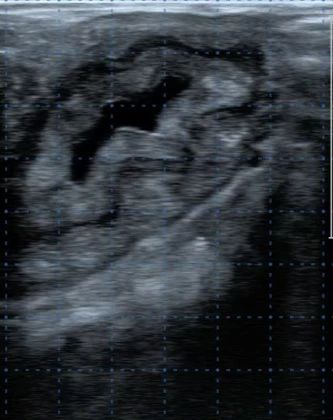

图6 定时输精时优势卵泡

图7 发情期卵巢状态

(左侧:子宫状态;右侧:成熟卵泡)